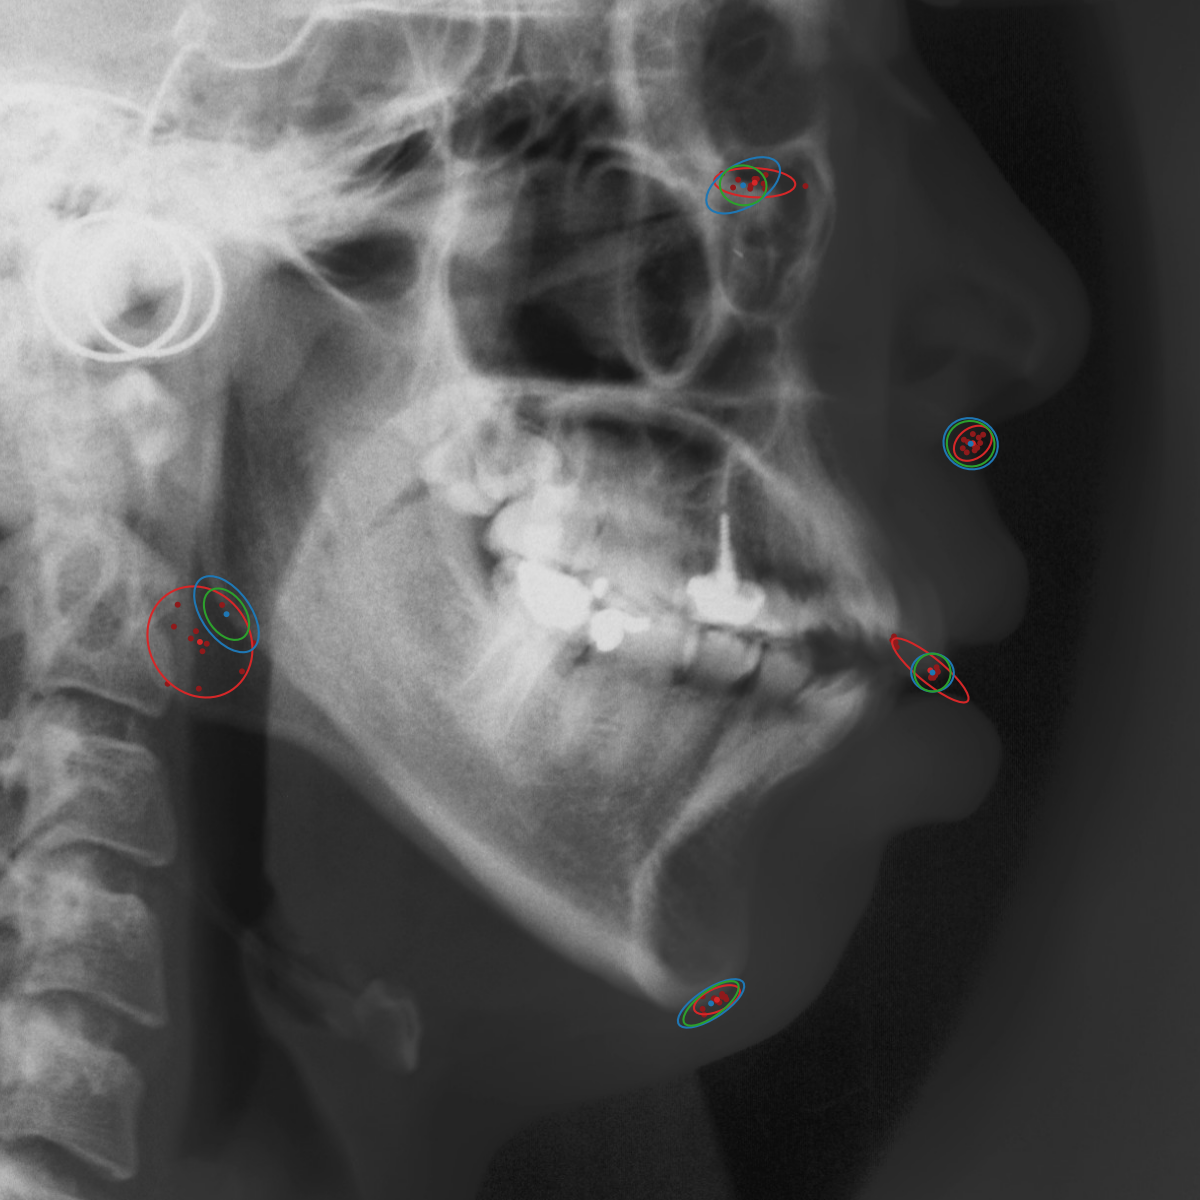

![]() | ![]() | ![]() |

Qualitative results of the landmark predictions as well as the predicted distributions for each landmark are presented in Fig. 7 for selected images. The visualized points are the 11 inter-observer annotations (dark red), their mean position (red) and the landmark predictions of our model (blue). The red ellipses represent the distributions fitted to the 11 annotations. The sample-based uncertainties and the dataset-based uncertainties are represented as blue and green ellipses, respectively. For the depicted images, it can be seen that most landmark predictions closely match to the mean of the 11 annotations, while the predicted uncertainties are similar to the annotation distributions. Discrepancy between the inter-observer annotations and uncertainties predicted by our method were primarily caused by landmarks that where difficult to recognize in a given image (landmark 2, bottom left and landmark 4, bottom middle) or by landmarks with high ambiguity (e.g., landmark 3, bottom middle and landmark 2 bottom right). Nevertheless, the predicted sample-based uncertainties are similar to the annotation distributions even when the dataset-based uncertainty of a landmark is too restrictive as, e.g., for landmark 2 (top middle), where both mandibles are visible due to the head being tilted.